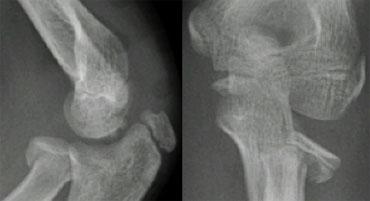

Một đường kẻ qua trung tâm cổ xương quay phải đi qua trung tâm của chỏm con, bất kể tư thế của bệnh nhân như thế nào, vì xương quay khớp với chỏm con (hình minh họa).

Trong trường hợp trật xương quay, đường này sẽ không đi qua trung tâm của chỏm con.

Ở bên trái, chúng ta thấy rằng đường quay-chỏm đi qua trung tâm của chỏm con trên mọi phim X-quang, mặc dù C và D không ở tư thế chuẩn.

Lưu ý gãy xương trên lồi cầu ở hình B.

Bên trái là các ví dụ khác về đường thẳng quay-chỏm.

Hình ảnh phía dưới bên phải cho thấy sự trật khớp rõ ràng của xương quay.

Radiographs of elbows at different ages. The Anterior Humeral line goes through the middle third of the capitellum .

Đường Humeral trước.

Một đường kẻ trên phim chụp nghiêng dọc theo bề mặt trước của xương cánh tay phải đi qua một phần ba giữa của chỏm con.

Đường này được gọi là đường Humeral trước.

Trong các trường hợp gãy xương trên lồi cầu, đường Humeral trước thường đi qua một phần ba trước của chỏm con hoặc ở phía trước chỏm con do sự uốn cong ra sau của đoạn xương cánh tay xa.

Ở bên trái, đường thẳng cánh tay trước đi qua một phần ba trước của chỏm con.

Điều này cho thấy các lồi cầu bị di lệch về phía sau (tức là gãy trên lồi cầu).

Đường thẳng quay-chỏm kết thúc phía trên chỏm con.

Điều này có nghĩa là xương quay bị trật khớp.

Bạn có nhận thấy gãy mỏm khuỷu không?

Bất cứ khi nào xương quay bị gãy hoặc trật khớp, hãy luôn quan sát kỹ xương trụ.